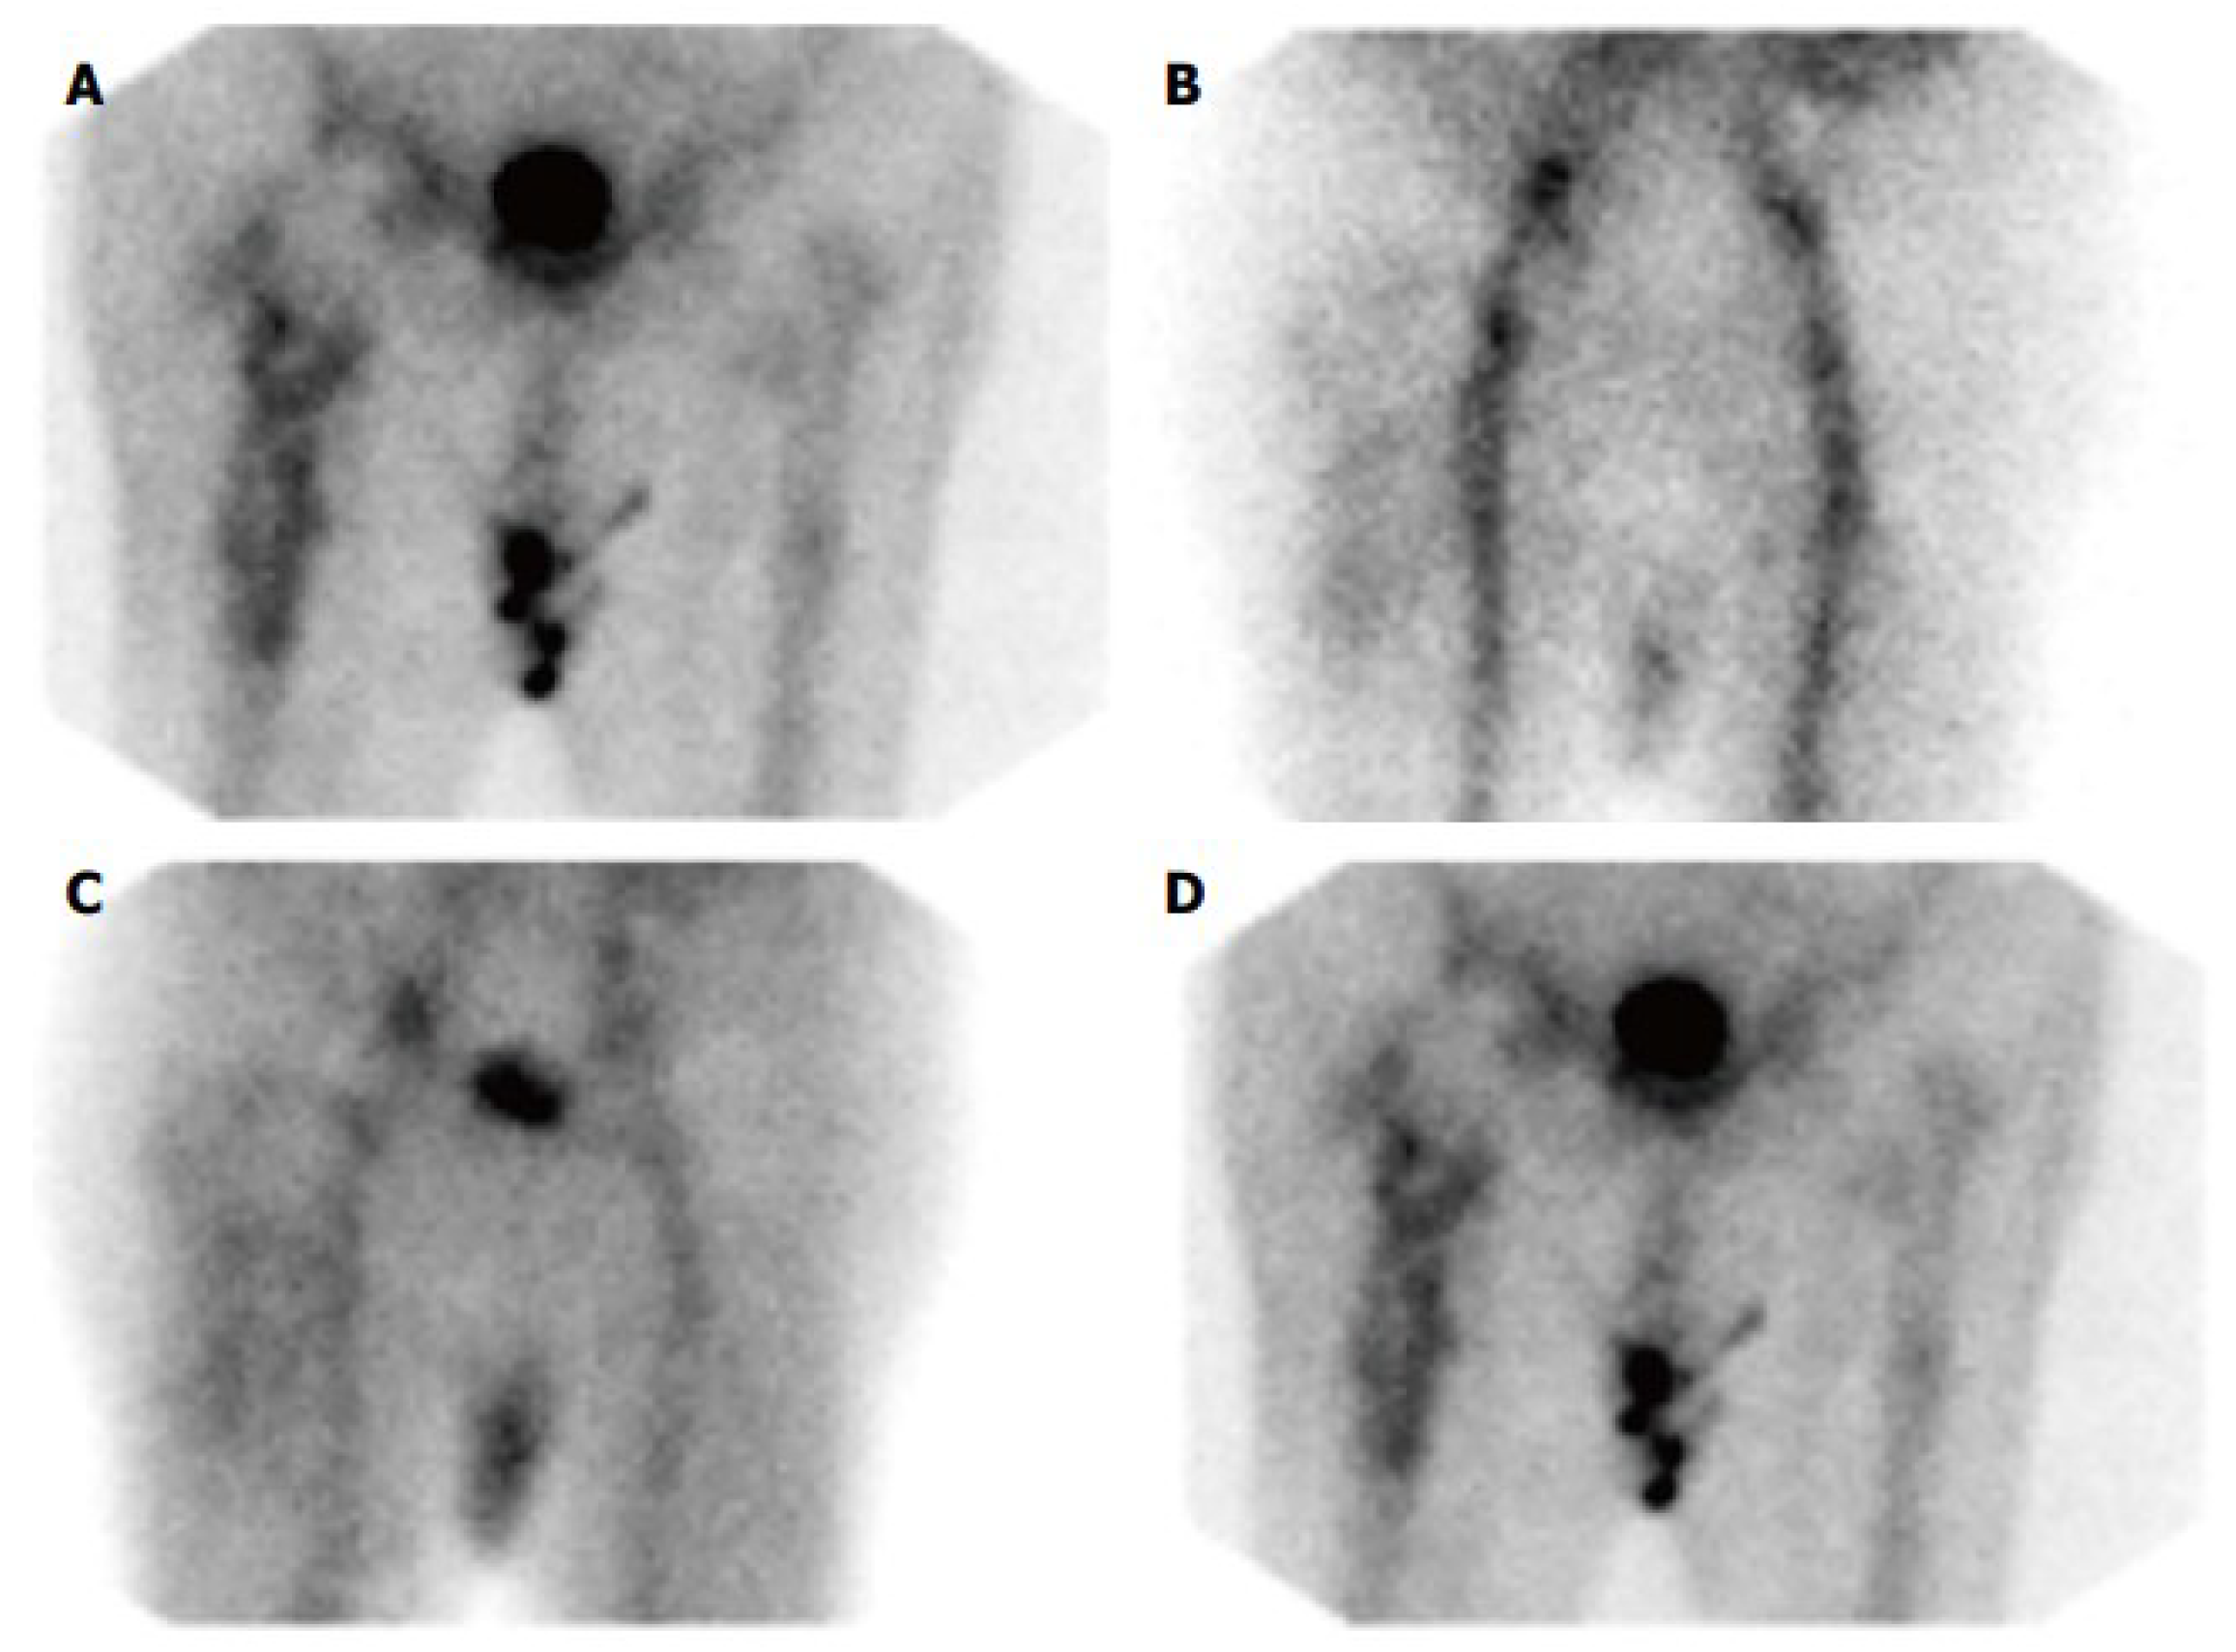

5.2. Leukocyte Scintigraphy

5.3. Anti-Granulocyte Scintigraphy

5.4. Combined Leukocyte and Bone Marrow Scintigraphy